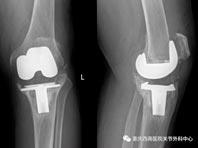

Китайцы напечатали на принтере новый сустав из редкого материала

Впервые в мире китайские ученые использовали технологию трехмерной печати костной ткани для восстановления коленного сустава, передает Вести.RU. Известно, что сустав, пораженный артритом, меняли 84-летнему пациенту. И в ходе работы применялся редкий металл...